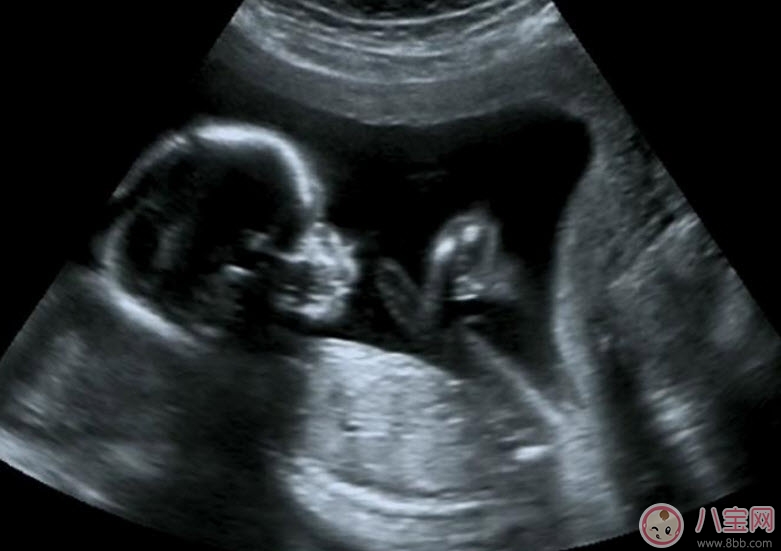

孕期B超作用是什么有什么講究,準媽媽們都知道在懷孕早期就要去做b超檢查肚子里的寶寶是否健康,那么孕早期B超作用是什么,孕早期B超有哪些講究呢,孕早期孕早期陰道B超對胎兒有影響嗎,應該最少做哪幾次b超呢,下面家佳樂課堂的小編就來說說:孕早期B超作用是什么有什么講究 孕早期陰道B超對胎兒有影響嗎。

B超既可以測量胎兒的各個部位,如胎頭大小、胎臀長度,也可以用于在早期妊娠來測定胎兒的具體懷孕時間(醫(yī)學上叫做孕周),測定胎頭的雙頂徑、頭圍、腹圍及胎兒股骨的長度等,這些數(shù)據(jù)可以判斷胎兒的生長發(fā)育情況。

B超可以有效發(fā)現(xiàn)胎兒畸形,一般在妊娠18-20周檢查可篩查胎兒有無畸形,為早期診斷早期采取措施提供依據(jù)。一旦發(fā)現(xiàn)胎兒畸形,早期容易終止妊娠,如消化道畸形,神經(jīng)管畸形,如無腦兒、脊柱裂等等,都可以及時采取流產(chǎn)、引產(chǎn)措施。

B超能夠直觀胎兒在母體內(nèi)的活動狀況,諸如呼吸情況、胎兒的運動、整個身體大的運動、肢體的運動、胎兒的吞咽動作等等,可以一覽無余。之外,通過觀察胎兒的張力是否良好,可以判斷胎兒在宮內(nèi)是否缺氧或者受到損害,準確預報胎兒安危。